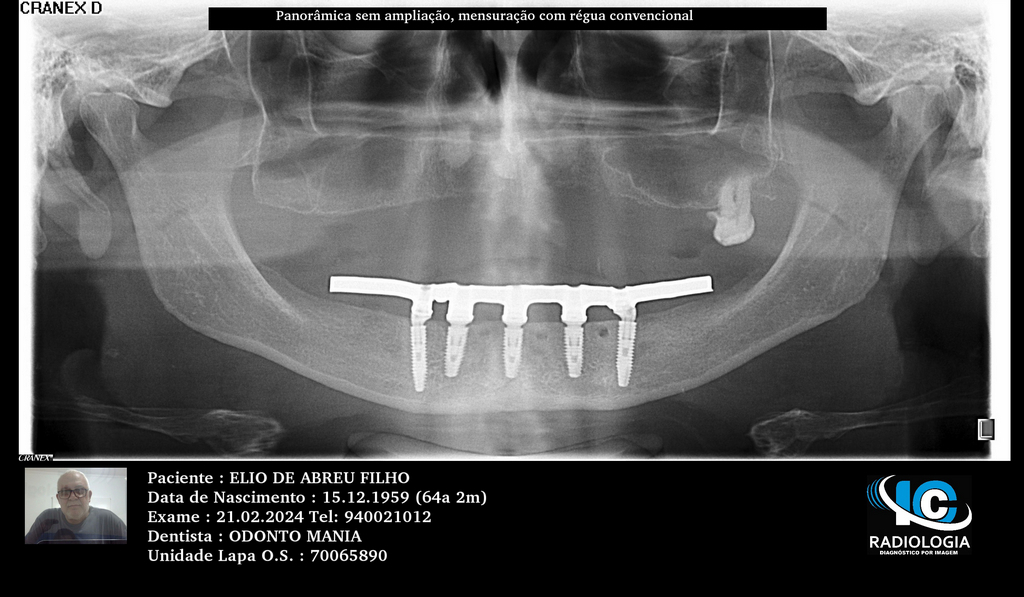

PRÓTESE TOTAL FIXA EM IMPLANTES

E.D.A.F